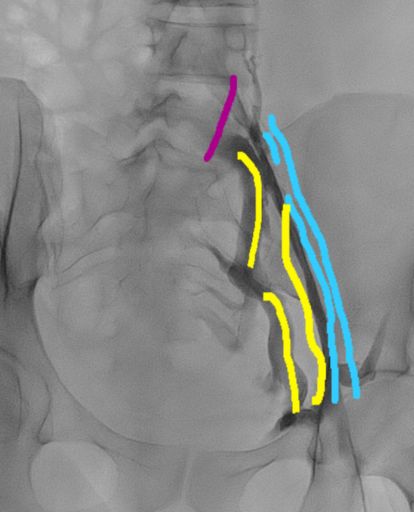

באיור ובבדיקת הדימות (CTV) הלחץ מסומן בחץ, כתוצאה מהלחץ זרימת הדם אינה מיטבית.

לכן, בכדי להמשיך ולנקז את הדם מהכליה, המערכת הוורידית שינתה את כיוון הזרימה בווריד השחלה במקום לכיוון הלב לכיוון האגן.

ולכן קיים עומס בכלי הדם הוורידיים באגן ובשלב מסוים עלול לגרום הגודש בוורידי האגן לכאב אגן כרוני.